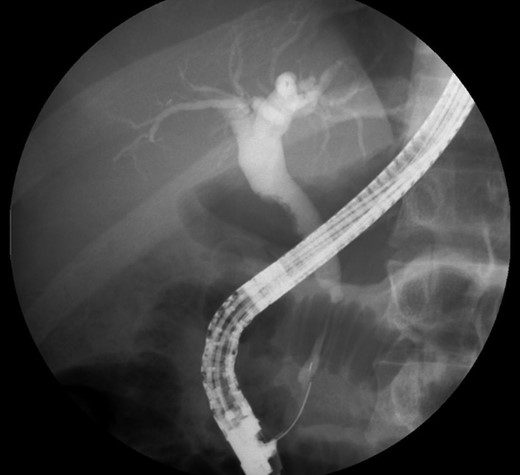

Endoscopic retrograde cholangio-pancreatography (ERCP) showed a lobular pancreas with an enhancing heterogeneous pseudonodular mass located in the pancreatic head. The main pancreatic duct (MPD) appeared a well-defined non-beaded narrowing duct. The common bile duct (CBD) showed no narrowing or strictures until the intrapancreatic portion which presented an irregular stenosis of 2 cm length and dilatation upstream the area of stricture.

Laboratory tests including IgG4, anti-smooth muscle antibody (ASMA), anti-mitochondrial antibody (AMA), anti-nuclear antibody (ANA), anti-neutrophil cytoplasmic antibody (ANCA), anti-Sjogren’s-syndrome-related antigen A/B, anti-Smith (anti-Sm), anti-dsDNA, complement C3/C4, CEA and CA 19-9 were all negative. Endoscopic ultrasound (EUS) revealed a heterogeneous parenchyma of the pancreatic head and an EUS-FNA was performed. The MRCP, on the other hand, suggested the existence of a distal cholangiocarcinoma, because of the sudden typical stenosis in the distal CBD with a general dilatation of the upper bile ducts (Fig. 3). Unfortunately, the biopsy was not enough to establish a definitive diagnosis.

ERCP. Heterogeneous pancreatic parenchyma and pseudonodular appearance of the pancreatic head. Wirsung duct with no stenosis or obstructions. Common bile duct with normal caliber until the intrapancreatic portion where a highly suspicious of malignancy 2 cm irregular stenosis is seen.

Specific features in CT imaging for AIP suspicion are focal or diffuse pancreatic enlargement with loss of the lobular shape (sausage-shaped pancreas), a low-density rim surrounding the pancreas and delayed homogenous enhancement during venous phase [8], which were not present. The patient presented an intrahepatic and distal bile duct dilatation but no pancreatic masses or abnormal enlargements and no delayed homogeneous enhancement. If non-classic CT abdominal features, ERCP can be very helpful in identifying the presence of a narrow stricture (>one-third of the MPD) or multiple non-contiguous strictures and absence of upstream dilatation from the stricture [9]. ERCP showed a pseudonodular mass in the head of the pancreas but the pancreatic duct presented no strictures or irregular stenosis. Only the intrapancreatic portion of the common bile duct presented an irregular 2 cm length stenosis and an upstream dilatation, pointing to cholangiocarcinoma.

Corticosteroid treatments should not be initiated until the possibility of malignancy is excluded, because some subtypes of PC and pancreatic lymphoma can respond to this therapy. CT scan features such as diffusely enlarged sausage-shaped pancreas without a clear ductal pancreatic dilatation render AIP more likely than PC, but if typical neoplastic features are present (e.g. intrapancreatic portion of the common bile duct with an irregular 2 cm length stenosis), patients should be considered as having a PC or cholangiocarcinoma [8]. The sudden stenosis of the distal common bile duct with a general upstream dilatation revealed in the MRCP and ERCP and also the absence of a long (>one-third length of the MPD) or multiple strictures of the MPD were major features for not considering de autoimmune etiology. Routine workup diagnosis for cancer was not negative and the patient undergone pancreatic resection.